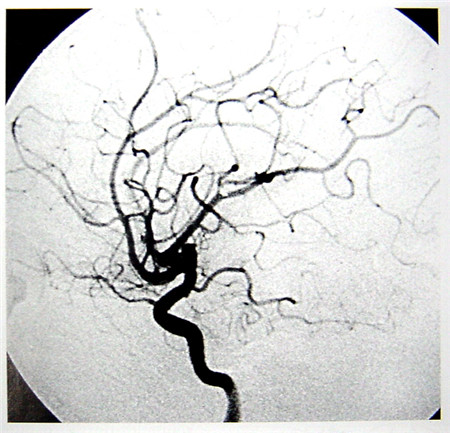

數字減影血管造影(DSA)簡介

數字減影血管造影技術(Digital Subtraction Angiography,DSA)是一種新的X線成像系統,是常規血管造影術和電子計算機圖像處理技術相結合的產物。DSA的成像基本原理是將受檢部位沒有注入造影劑和注入造影劑后的血管造影X線熒光圖像,分別經影像增強器增益后,再用高分辨率的電視攝像管掃描,將圖像分割成許多的小方格,做成矩陣化,形成由小方格中的像素所組成的視頻圖像,經對數增幅和模/數轉換為不同數值的數字,形成數字圖像并分別存儲起來,然后輸入電子計算機處理并將兩幅圖像的數字信息相減,獲得的不同數值的差值信號,再經對比度增強和數/模轉換成普通的模擬信號,獲得了去除骨骼、肌肉和其它軟組織,只留下單純血管影像的減影圖像,通過顯示器顯示出來。通過DSA處理的圖像,使血管的影像更為清晰,在進行介入手術時更為安全。

數字減影血管造影DSA腦血管圖像顯示 核磁共振MRI掃描腦組織圖像